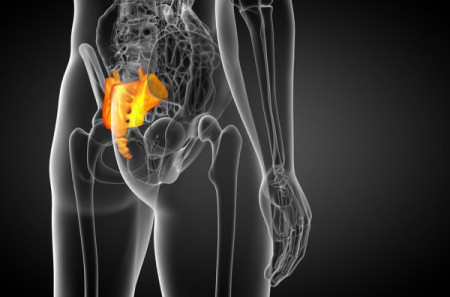

Хоча сучасна людина вже давно втратила хвіст, куприк – маленька трикутна кістка внизу хребта – все ще нагадує про наш еволюційний зв’язок із предками. Ця рудиментарна структура – залишок хвоста, який розвивається у людини ще на ембріональній стадії, а потім зникає.

За словами Крістал Кеніг, доцента кафедри антропології Університету Південної Юти, людський куприк – «спадок далекого предка, який мав хвіст», пише ТСН. Попри свою непомітність, він виконує кілька важливих функцій – слугує точкою кріплення м’язів і зв’язок тазового дна, що підтримують сечовий міхур, пряму кишку та матку, а також допомагає зберігати рівновагу у сидячому положенні.

За словами Крістал Кеніг, доцента кафедри антропології Університету Південної Юти, людський куприк – «спадок далекого предка, який мав хвіст», пише ТСН. Попри свою непомітність, він виконує кілька важливих функцій – слугує точкою кріплення м’язів і зв’язок тазового дна, що підтримують сечовий міхур, пряму кишку та матку, а також допомагає зберігати рівновагу у сидячому положенні.